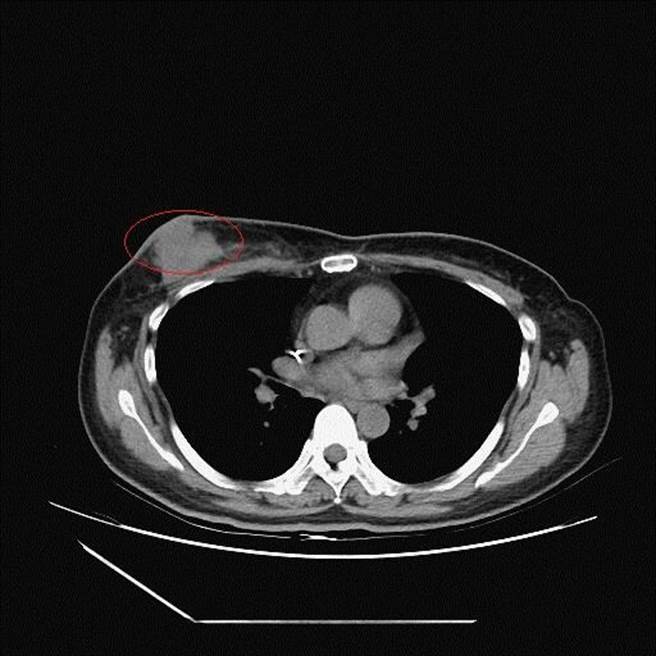

李忠懷表示,經乳房超音波、粗針切片及電腦斷層檢查,證實個案為第三期的乳癌併發腋下淋巴結轉移,乳房腫瘤5公分、淋巴結腫瘤3.2公分,推估腫瘤已存在數月,並非打疫苗引起;目前正透過化療將腫瘤縮小後,再手術切除。